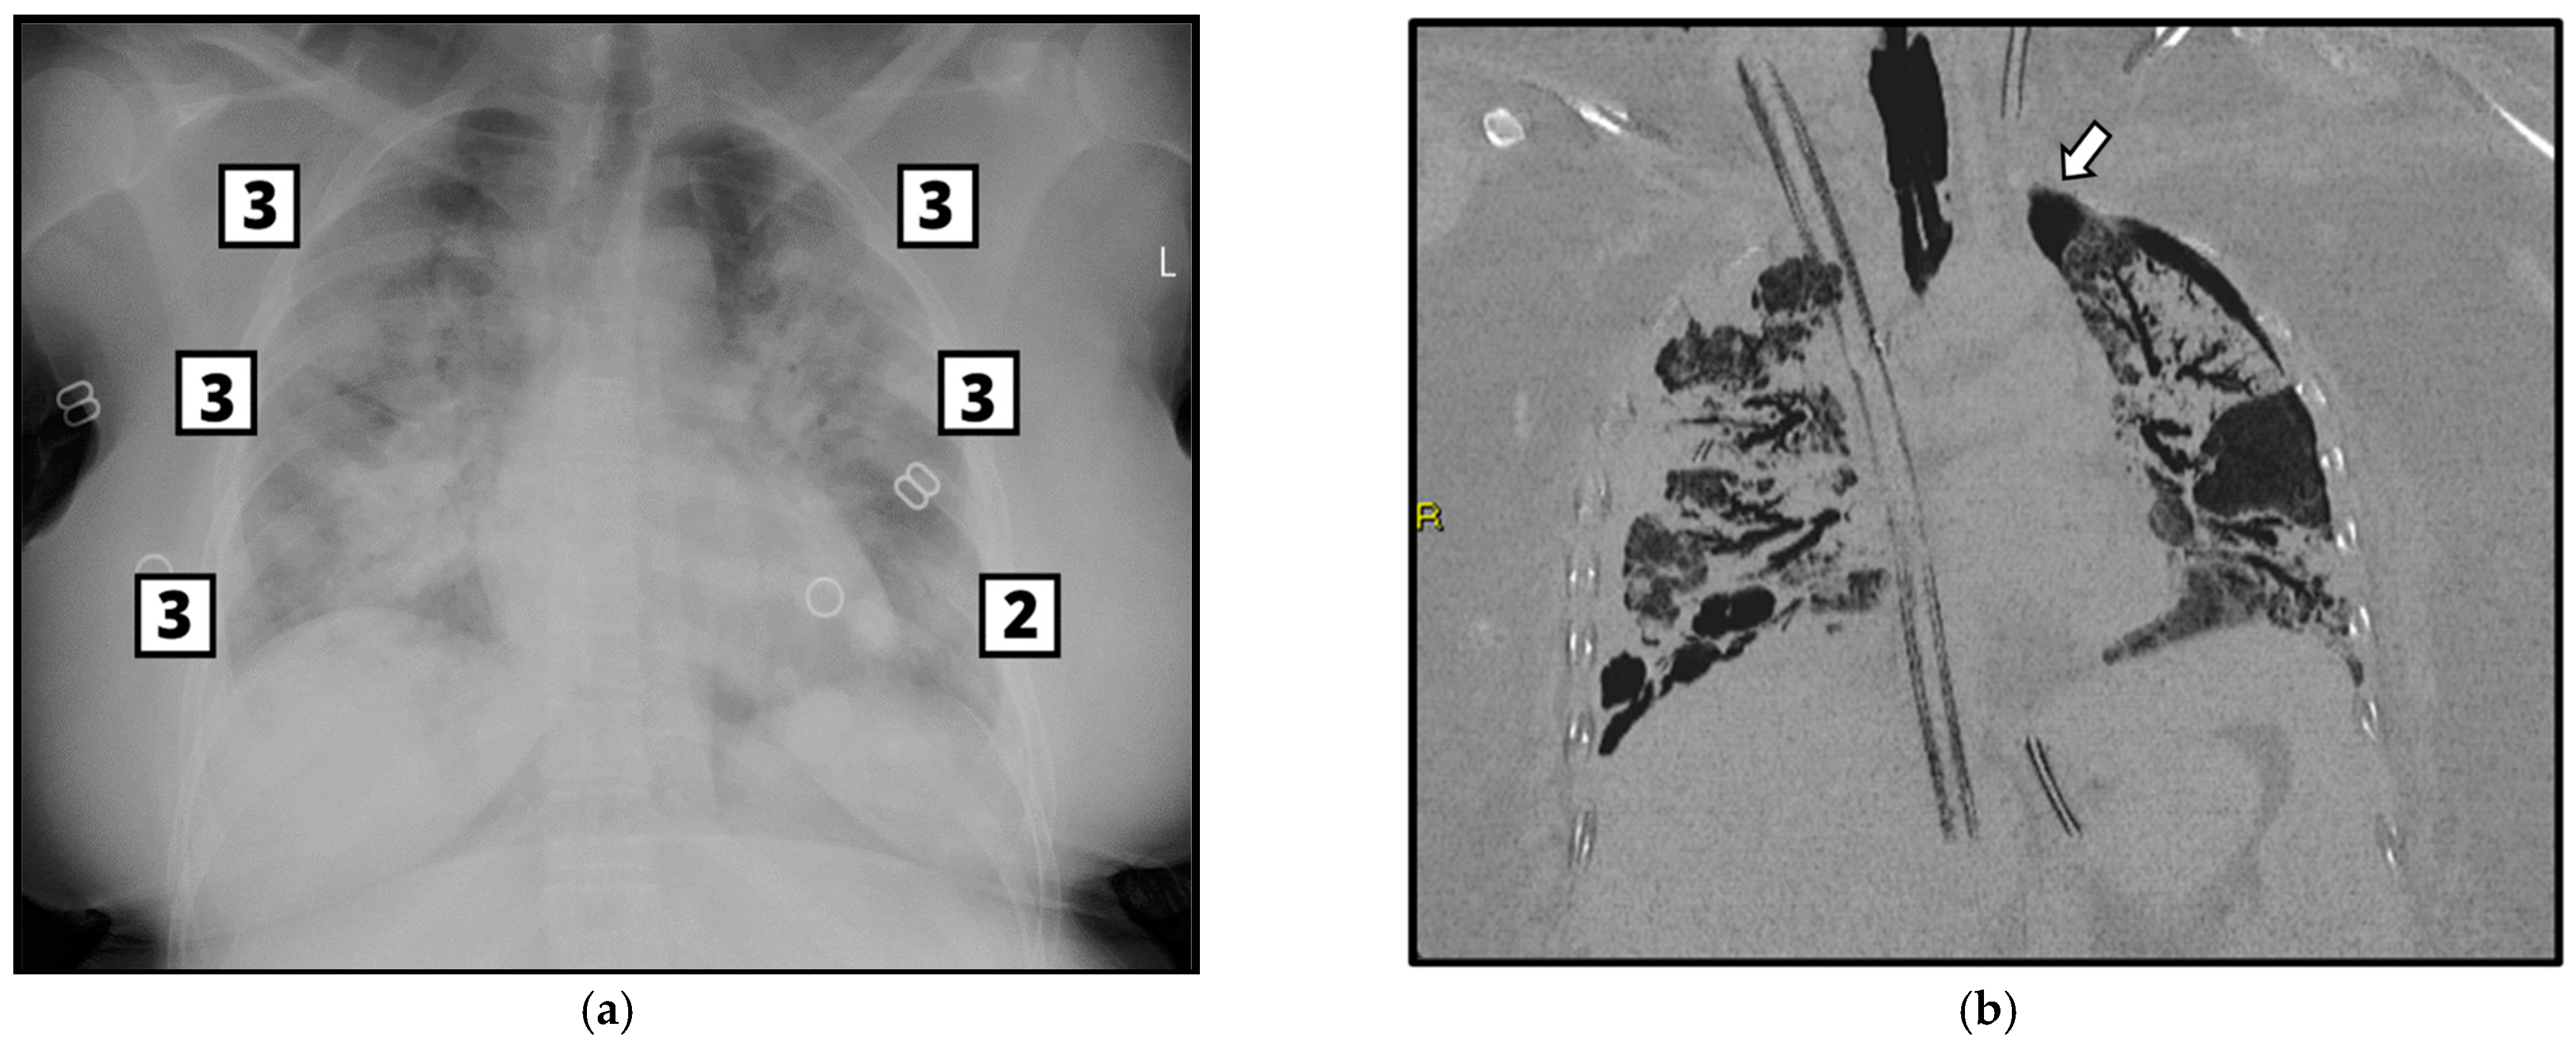

2.3. Imaging Acquisition and Analysis—CXR and CT